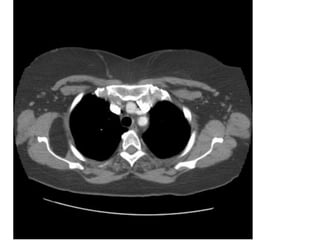

CÁC LÁT CẮT

CT NGỰC BÌNH THƯỜNG

A

D